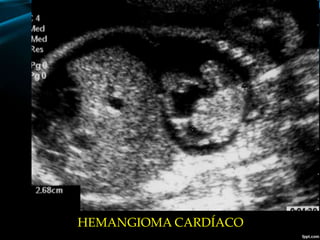

-TUMORES CARDIACOS.

HEMANGIOMA CARDÍACO